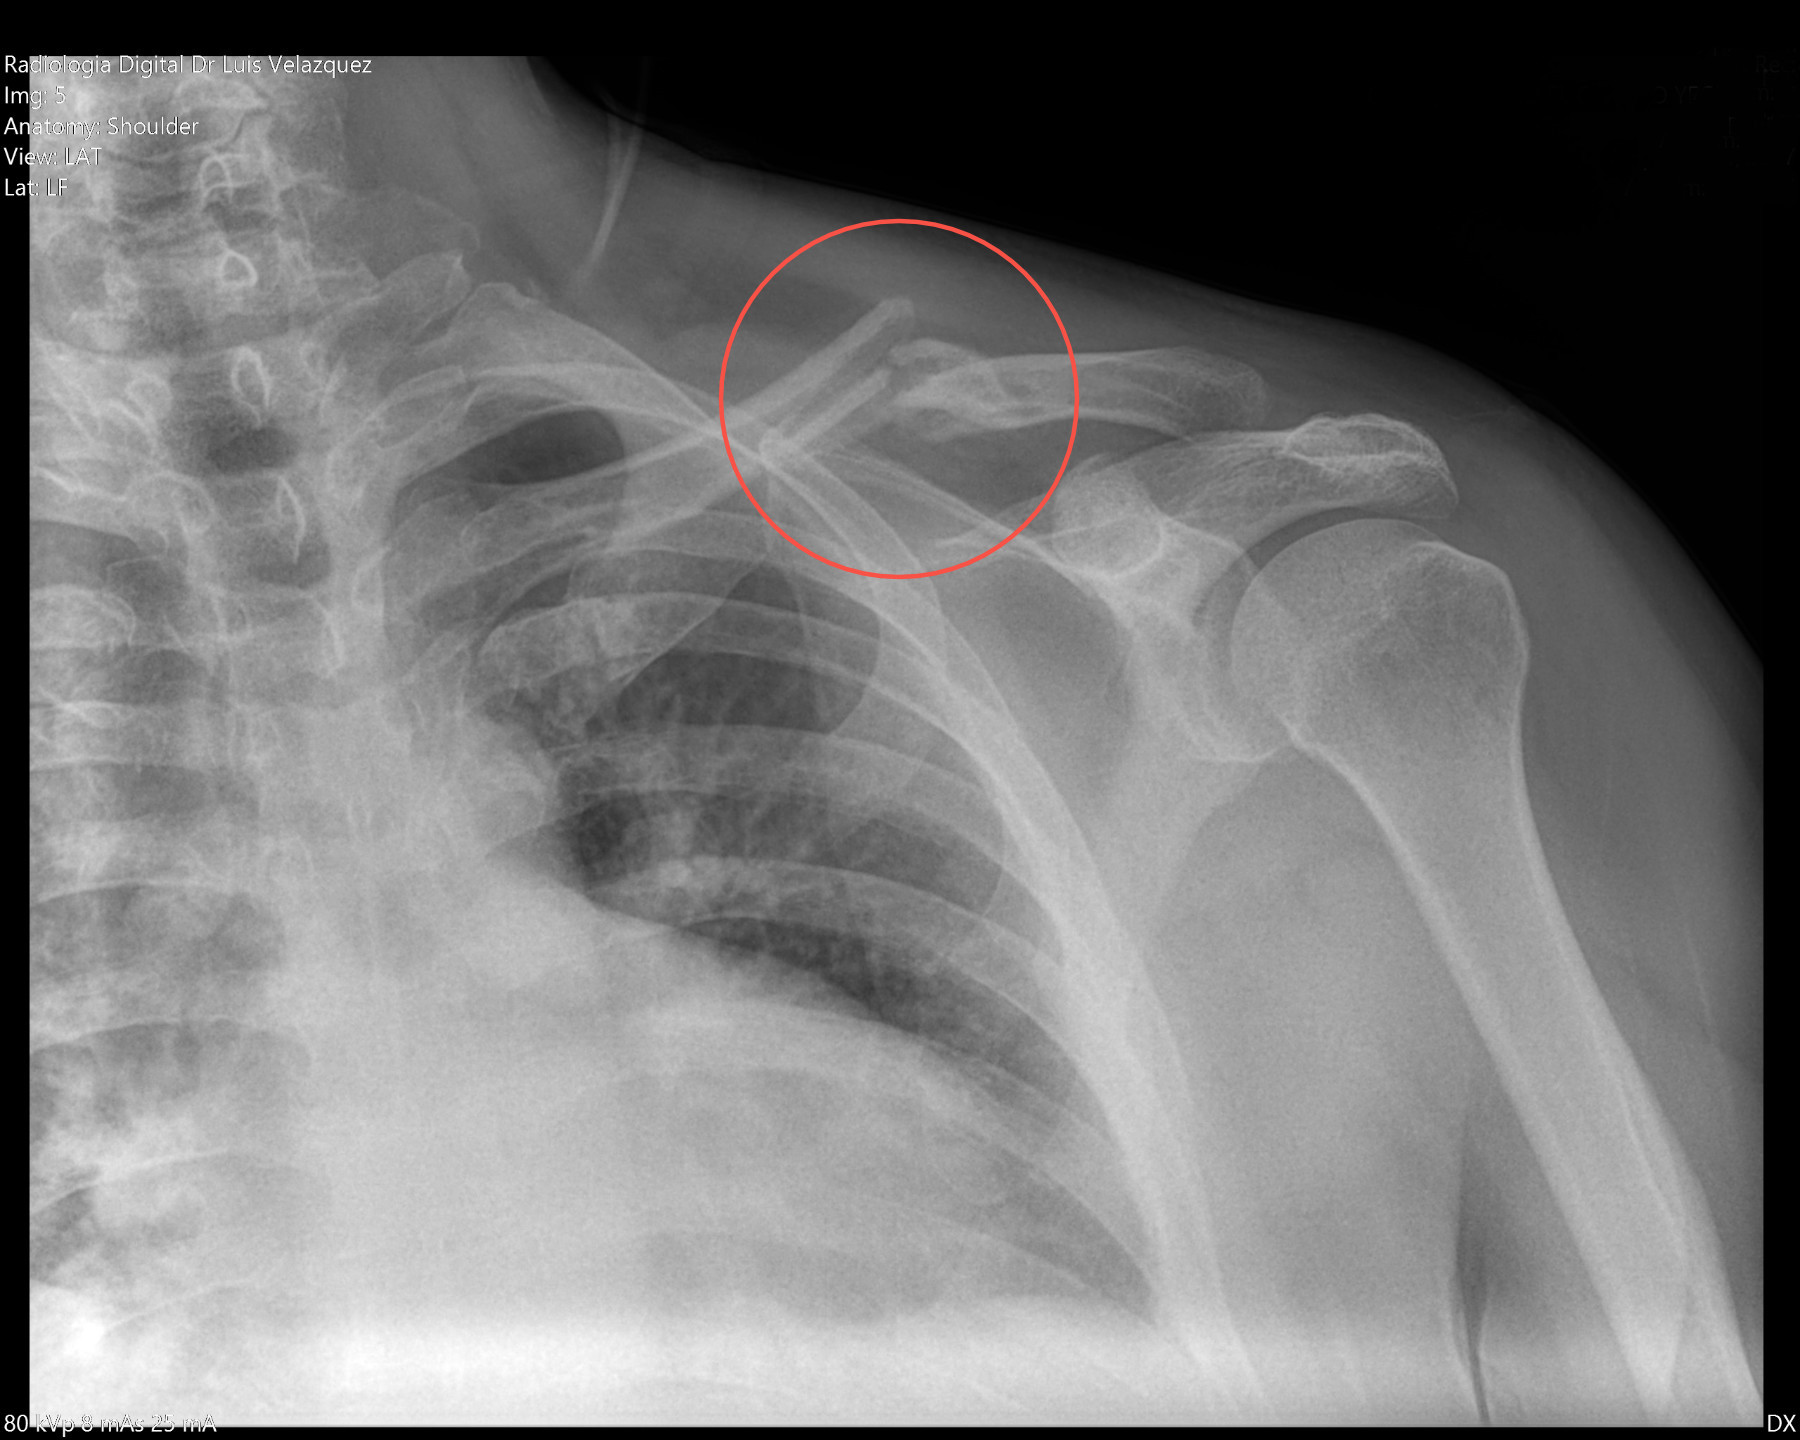

Radiología Digital como Herramienta Complementaria en el Dictamen de Bienes Muebles

Desde el descubrimiento de los rayos “X” y las placas radiográficas por Wilhelm Conrad Roentgen y su posterior difusión a través de la Asociación Físico médica de Wurzburg el 28 de diciembre de 1895, que fue la primera asociación que habló de los nuevos rayos que podían penetrar el cuerpo y fotografiar los huesos, ha habido muchos cambios tanto en la forma de obtener, procesar e incluso en la forma de visualizar, manejar y almacenar las placas radiográficas.